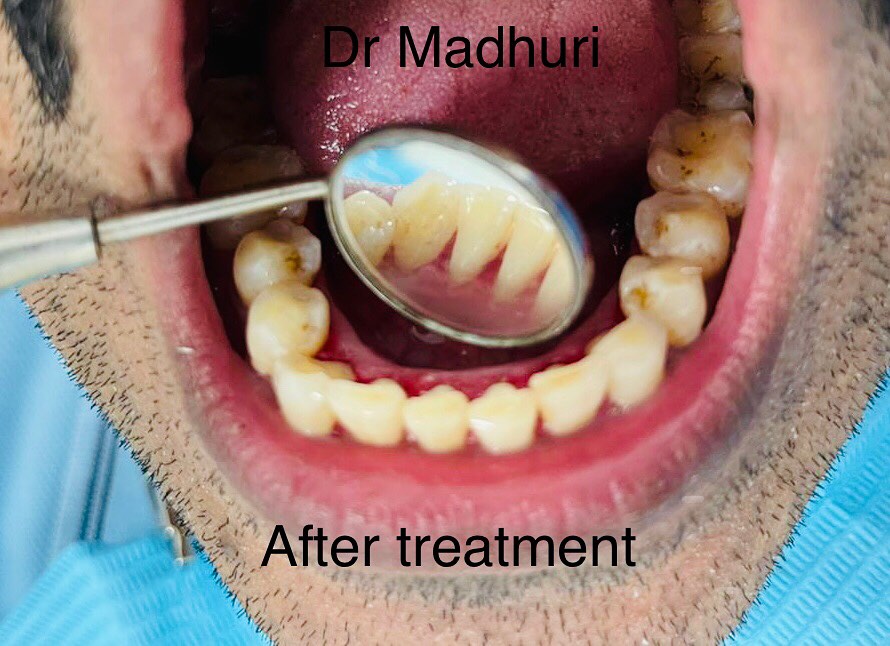

Explore Our Clinical Dental Gallery

Welcome to our official treatment gallery, showcasing the real results, smile transformations, and advanced dental care delivered by Dr. Madhuri. We believe that a picture is worth a thousand words when it comes to the art and precision of modern dentistry. Review our comprehensive visual portfolio below to see how our dedicated care helps patients achieve healthy, beautiful, and confident smiles.